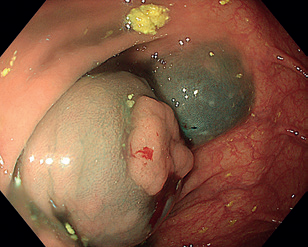

Obr. 3 Stopkatý polyp 0‑Ip zobrazený metodou Narrow Band Imaging.Endoskopická polypektomie (EPE) představuje základní a nejčastěji využívanou terapeutickou proceduru v oblasti gastrointestinální endoskopie. Princip EPE spočívá v naložení polypektomické kličky na stopku stopkatého polypu (0‑Ip), která je tvořena zdravou sliznicí a submukózou, následně je tato stopka přerušena kombinací mechanické síly při uzavření smyčky a elektrického koagulačního proudu (technika známá jako „hot snare“) (obr. 3–5). U rizikových polypů (šíře stopky nad 10 mm či velikost polypu nad 20 mm) se pro minimalizaci rizika krvácení doporučuje před resekcí stopku infiltrovat roztokem adrenalinu, popř. na stopku naložit endoklipy nebo použít odnímatelnou smyčku, známou též jako „endo­loop“, která po resekci polypu zůstává na stopce (obr. 6). EPE se často využívá i pro resekci malých plochých nebo přisedlých lézí (0‑IIa, 0‑Is) s průměrem ≤ 10 mm (obr. 7), a to obvykle pouze v mechanickém režimu bez využití elektrické koagulace (technika známá jako „cold snare“). Tato metoda snižuje riziko pozdějšího krvácení a vzniku koagulačního syndromu. „Resekce“ diminutivních lézí pomocí biop­tic­kých kleští, běžně používaná v minulosti, byla do značné míry opuštěna pro riziko inkompletní resekce a nahrazena právě „cold snare“ polypektomií. Klešťovou resekci je nadále možno použít jen u lézí do velikosti 3 mm. Použití elektrokoagulačních kleští („hot forceps”) se obecně nedoporučuje.